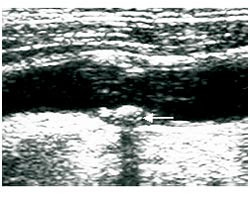

Forskjellige måter å klassifisere plakkekkogenisitet på er i bruk, og begrepsbruken er til dels forvirrende. Mange klassifiserer plakkekkogenisitet i fire kategorier (i engelsk litteratur kalt echolucent, predominantly echolucent, predominantly echogenic og echogenic) (5, 7) – (9), hvor kategori 1 er plakk med ren lavekkogen struktur (fig 1) og kategori 4 er plakk med høyekkogen struktur (fig 2). Noen bruker tre kategorier og andre benevnelser (10) – (12). Andre klassifiserer plakk som heterogene eller homogene, hvor heterogen brukes for å beskrive plakk av blandet ekkogenisitet med varierende innhold av lavekkogene soner, mens begrepet homogen beskriver plakk med middels eller høy plakkekkogenisitet (13, 14). Imidlertid kan begrepet homogent også brukes for å beskrive et plakk med jevn ekkostruktur, dvs. at et homogent plakk kan være både lavekkogent og høyekkogent (5, 10).

Validering av ultralydundersøkelse av plakk er blitt gjort i flere studier (7, 12, 13, 15, 16). Wolverson og medarbeidere beskrev i 1983 at plakk med stor, lipidrik kjerne var lavekkogene, mens områder med fibrose og kalk gav mye ekko (15), og de samme funnene er senere bekreftet av andre.

Ferske, uorganiserte tromber er lavekkogene strukturer som kan være vanskelige å skille fra lipidrike plakk. De mangler imidlertid fibrøs kapsel. Fargedoppler brukes til å skille et lavekkogent plakk eller en trombe fra karlumen.